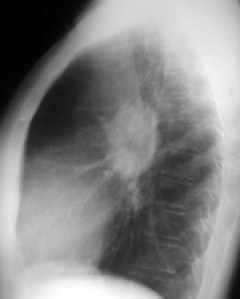

Mostramos un paciente con adenopatías en la ventana aorto-pulmonar (flecha), que también presenta adenopatías hiliares.

Proyección lateral del mismo paciente que muestra un aumento de densidad correspondiente a las adenopatías hiliares y en la ventana aorto-pulmonar.